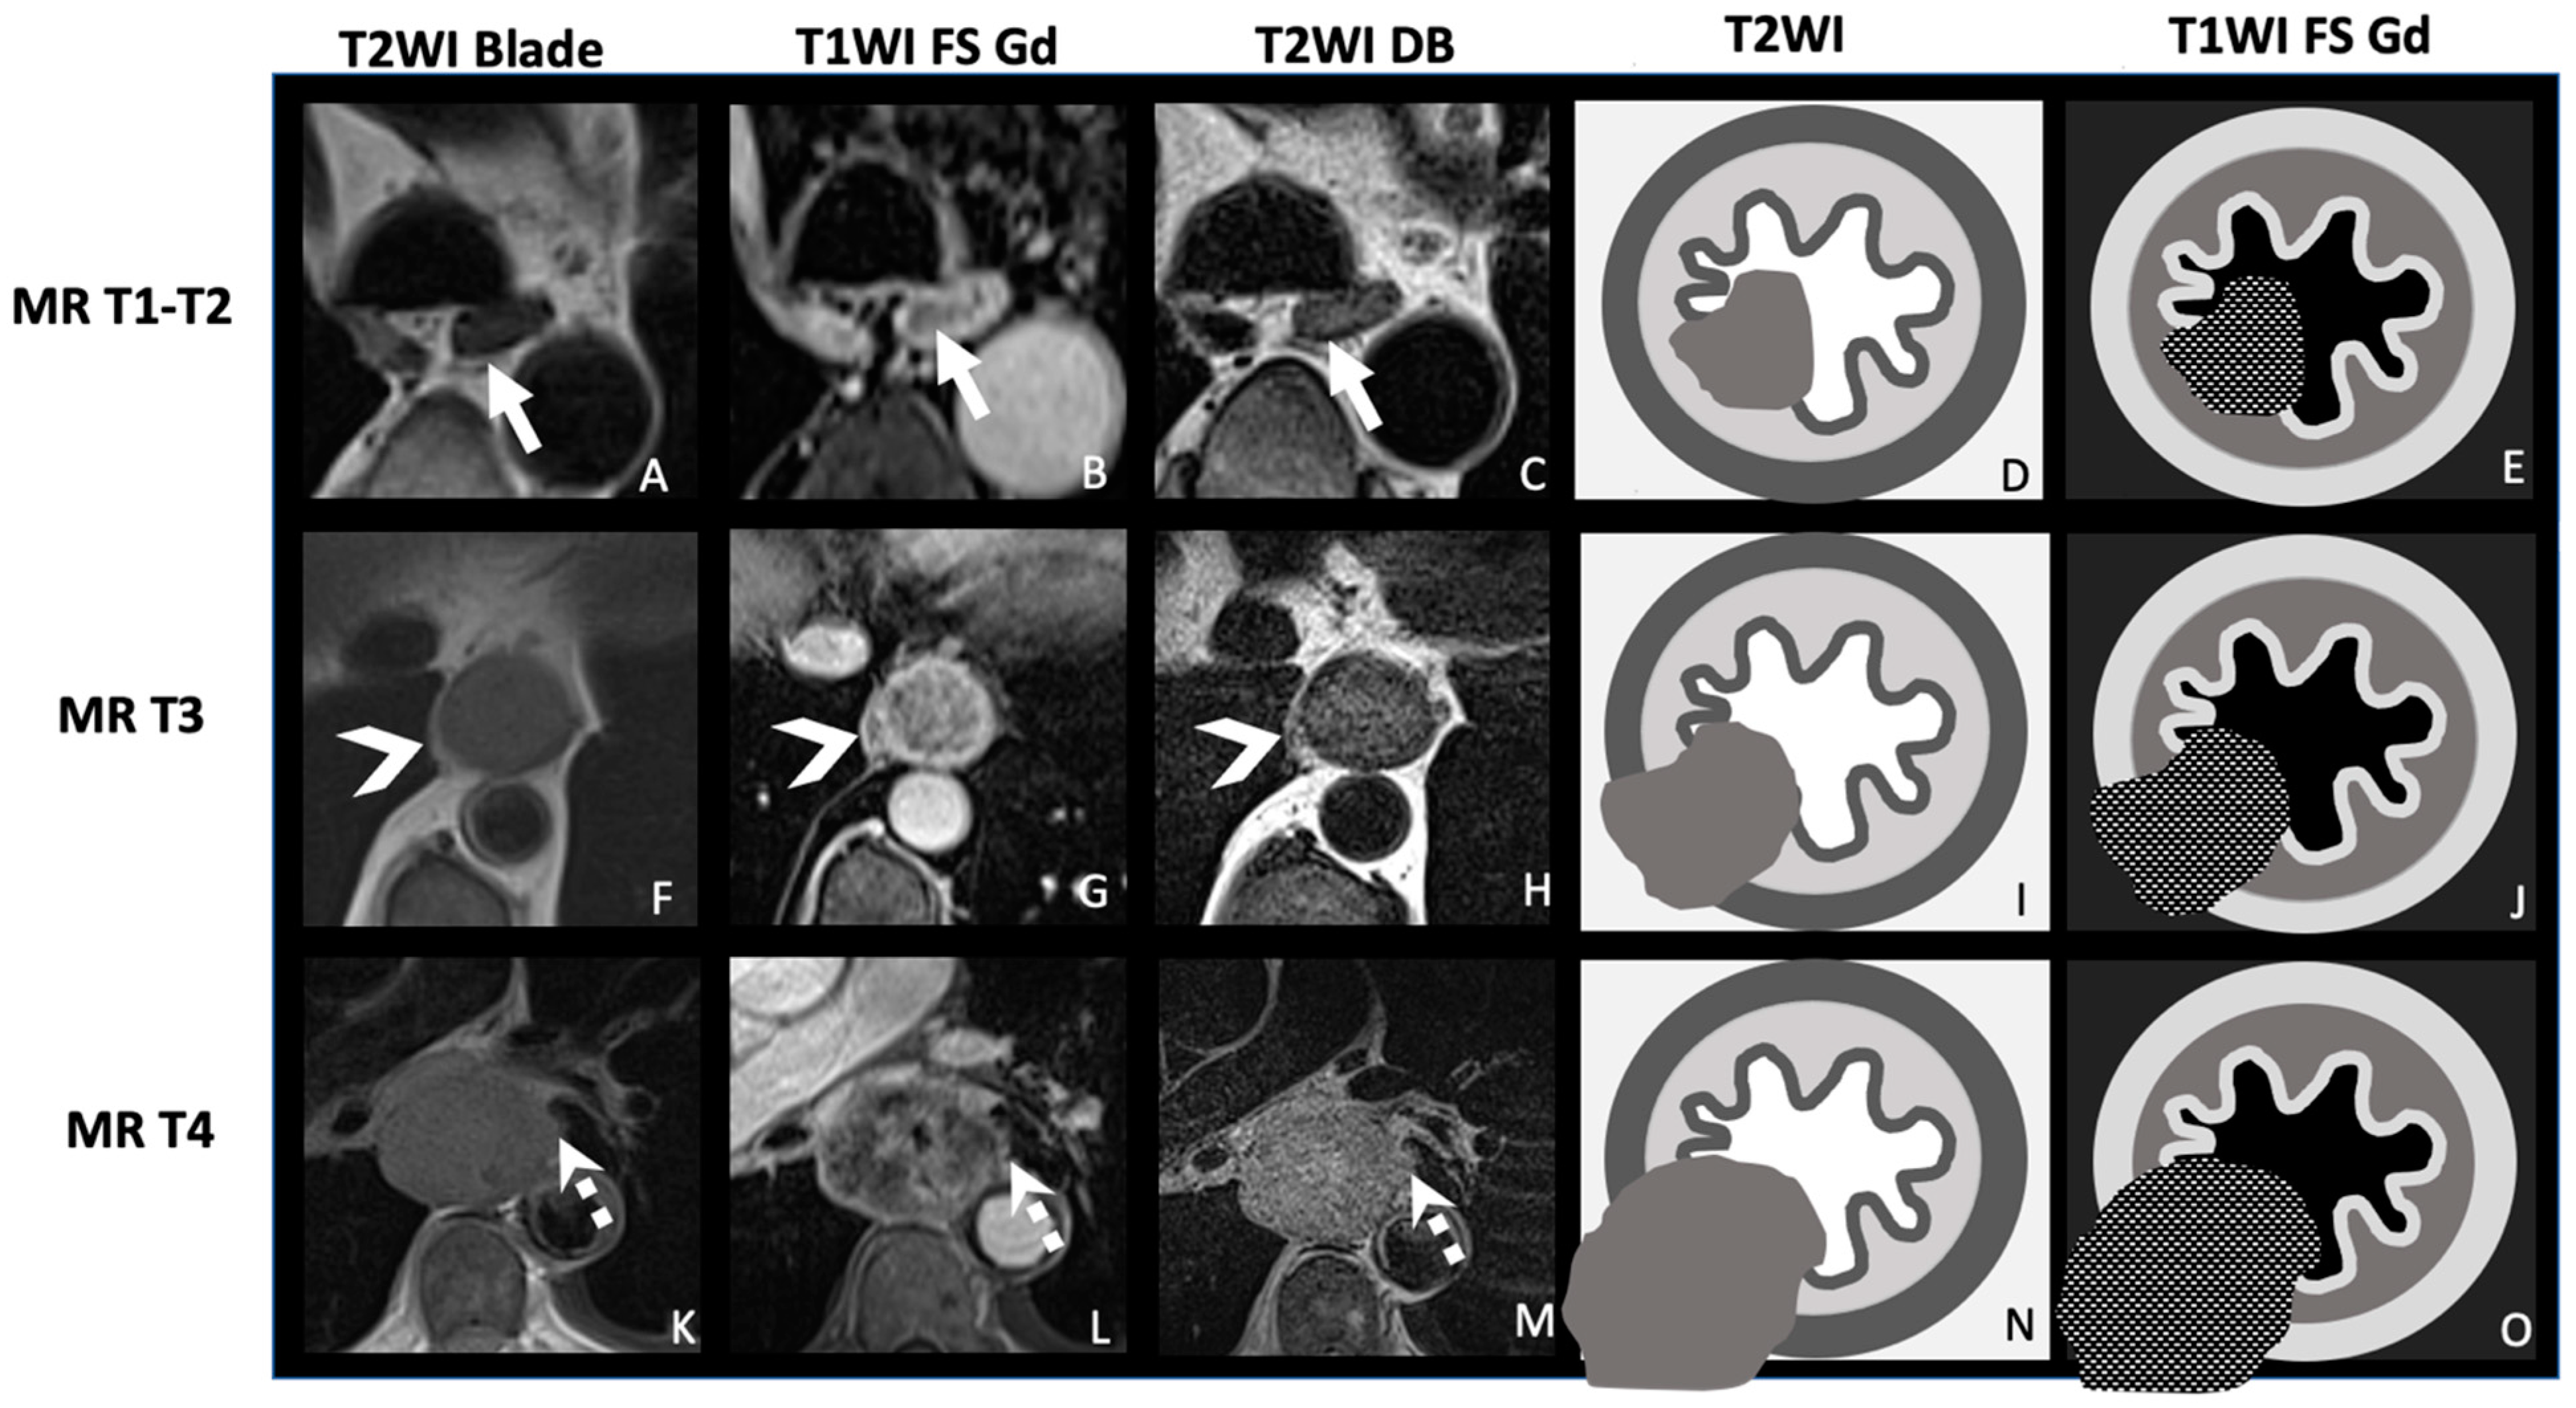

| TNM Histo-Pathologi Definition (According to AJCC/UICC 8th Edition) | MRI TNM Staging |

|---|---|

| T1: Tumor invades the submucosa | MR-T1-T2: Tumor signal intensity is confined to esophageal wall without extension to peri-esophagus fat |

| T2: Tumor invades the muscularis propria | |

| T3: Tumor invades adventitia | MR-T3: Tumor invades the peri-esophagus fat tissue |

T4: Tumor invades adjacent organ

| MR-T4: Tumor invades adjacent organs

|

| N+: Regional lymph nodes metastasis | MRI-N+: Round, Intermediate to high T2 signal, heterogeneous T1 Gd, >5 mm small axe |

| M+: Distant metastases | MRI-M+: Distant lymph node (sus-clavicular e.g.), liver metastases or other organ metastases |